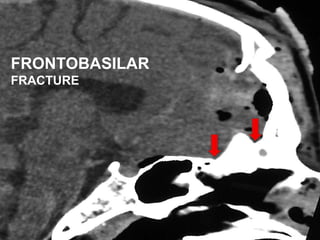

• #8 FRONTAL SINUS fracture is defined as fractures involving one or more sinus wall fracture however,

• #9 FRONTOBASILAR Fractures are fracture extending into or beyond the ethmoid sinuses & cribriform plate which is a distinct & completely different & more complex injury.

• #21 A fracture in the posterior table is not an absolute indication for surgery unless it is displaced or there are associated intracranial findings

• #22 For the Intracranial injuries, Pneumocephalus is often seen near the fracture linesAlthough it does raise dural injury, pneumocephalus adjacent to a non displaced posterior table fracture does not demand surgery unless CT fails to document resolution.